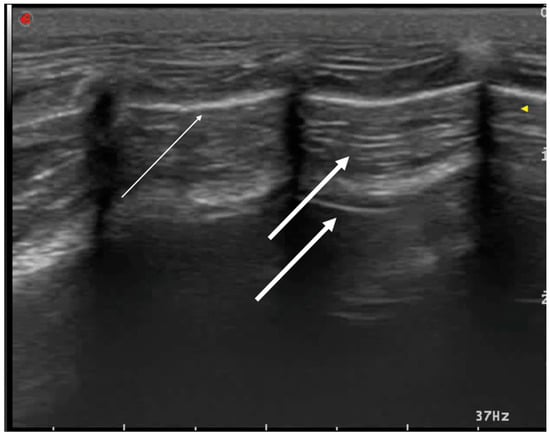

3.2. Pulmonary Diseases

3.2.2. Cardiogenic Pulmonary Edema